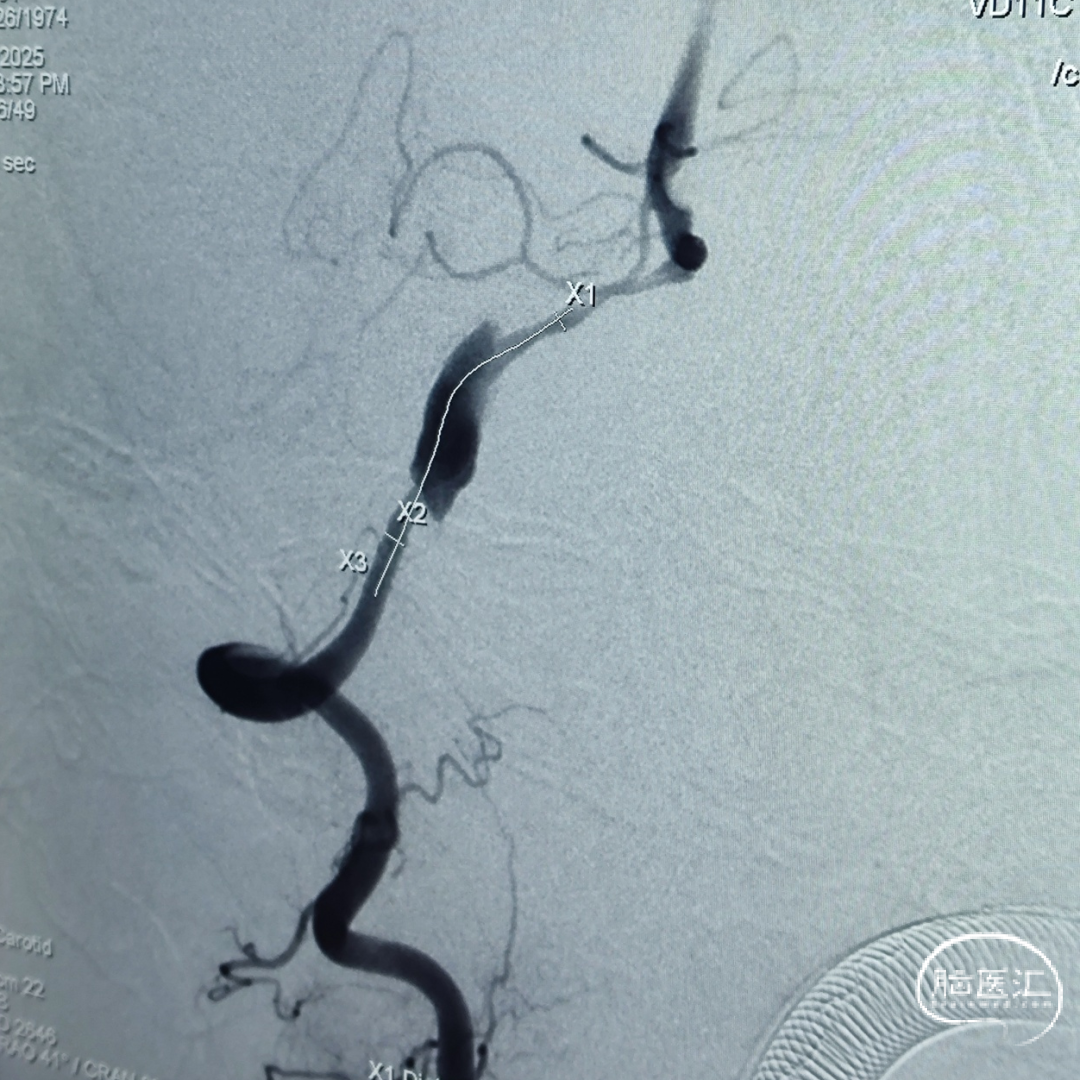

远端锚定点脉前起始近端;近端锚定点海绵窦段。

载瘤动脉远端血管直径:3.23 mm

载瘤动脉近端血管直径:4.17 mm

选用4.25mm*25mm 强易达(Choydar)密网支架。

左侧椎动脉劣势,颅内段纤细;右侧V4段夹层,血管狭窄。

载瘤动脉远端血管直径:1.50mm

载瘤动脉近端血管直径:1.83mm